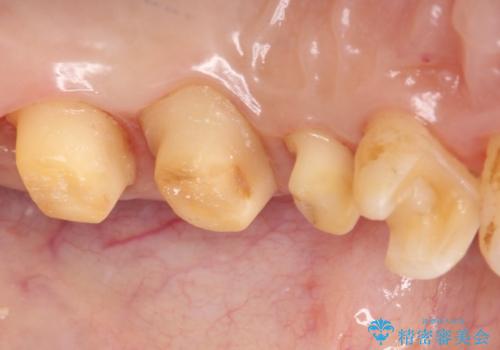

- 奥歯の銀歯をセラミックの白い歯にして、しみる症状も改善したいとのことで来院された患者様です。

知覚過敏の症状が強い歯と、銀歯の範囲や銀歯の下のむし歯が大きい歯は、インレー修復では対応が難しいためオールセラミッククラウンで、インレー修復で対応が可能な歯ではセラミックインレーにて修復することとしました。